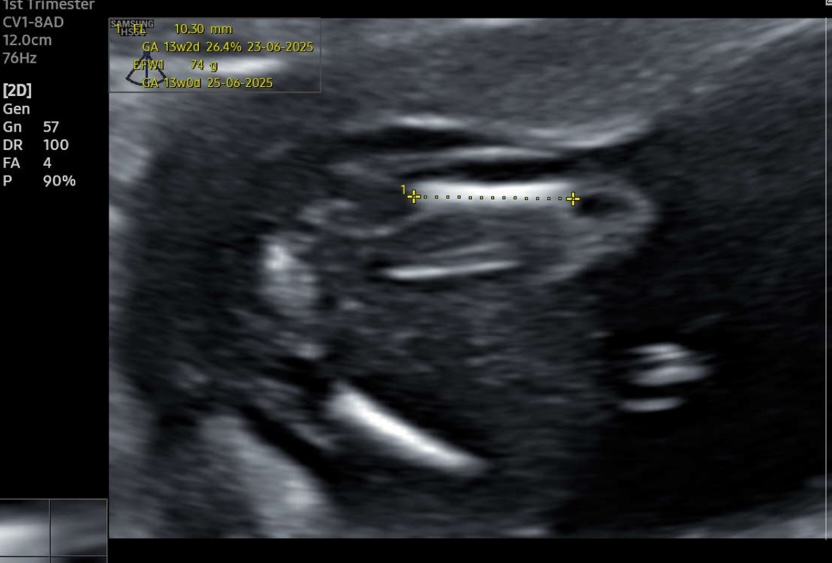

We sway girl and got a scan today with 13.4 weeks. I was hoping to see girl but my feeling say it’s another boy. Please tell me what you think. Boy or swollen girl?

I have found more pictures that are maybe useful. Unfortunately no clear picture from the side with a nub what makes me think boy. Please help me with your guesses:-)Attachment 43795Attachment 43796Attachment 43797Attachment 43798Attachment 43799Attachment 43800Attachment 43801Attachment 43802